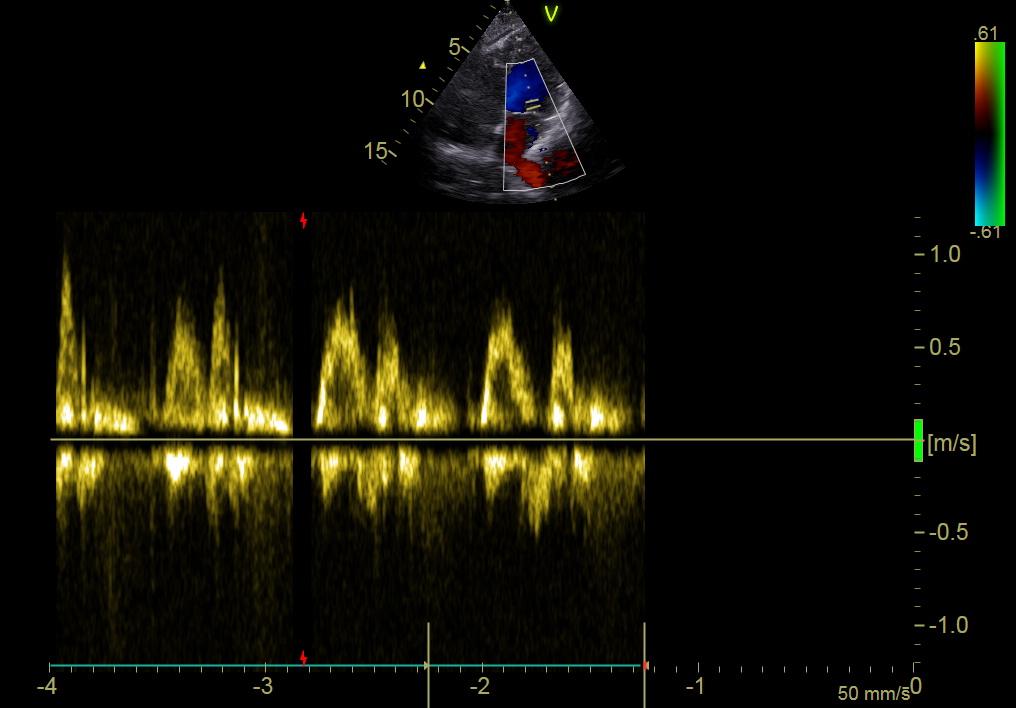

Before starting chemotherapy, we needed to make sure my heart was healthy enough to endure it. So I went to the hospital for a full cardiological exam: an electrocardiogram followed by an echography. We didn’t expect anything to show up - I have never suffered from cardiological issues - but basically, like with everything, “you never know”.

The data for this day are an electrocardiogram on the usual pink paper, and an echocardiogram, which is used to highlight the structure, function, and blood flow of the heart. The second image shows a color flow doppler, with in blue the blood that flows from the probe and in red the blood that flows towards it. Everything was healthy and ready to sustain chemotherapy.